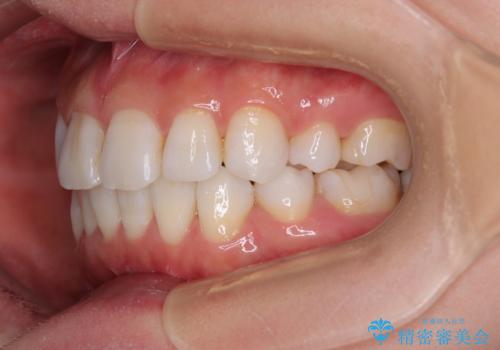

- 上下前歯の後戻りを気にして来院された患者様です。

インビザラインでの治療を希望されていて、デコボコの程度が中等度であり、安価なパッケージにて対応可能と判断されたため、インビザライン・モデレートを用いて矯正治療を行うこととしました。